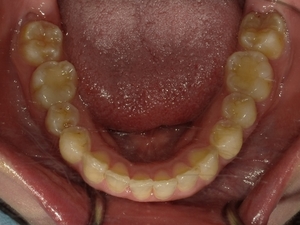

ガタガタとした歯並びや八重歯(叢生)CASE53